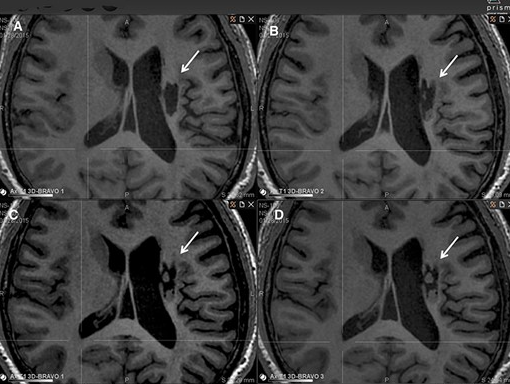

影像學檢查:在 6 個月的隨訪中,所有 9 名受試者均觀察到新組織,源自腦軟化梗塞腔。該腔內(nèi)組織外觀具有以下特征:短期活力(術(shù)后第一次 MRI 與基線相比的組織外觀)—9 例中有 9 例;生長(術(shù)后至少兩次 MRI 中新組織增加)—6 例中有 6 例;穩(wěn)定(術(shù)后至少兩次 MRI 中新組織沒有變化;即生長平臺期,最長為 24 個月)—6 例中有 5 例;無法獲得 24 個月后的長期活力。

(A)基線時,(B) 6 個月隨訪時,(C) 12 個月隨訪時,(D) 24 個月隨訪時。